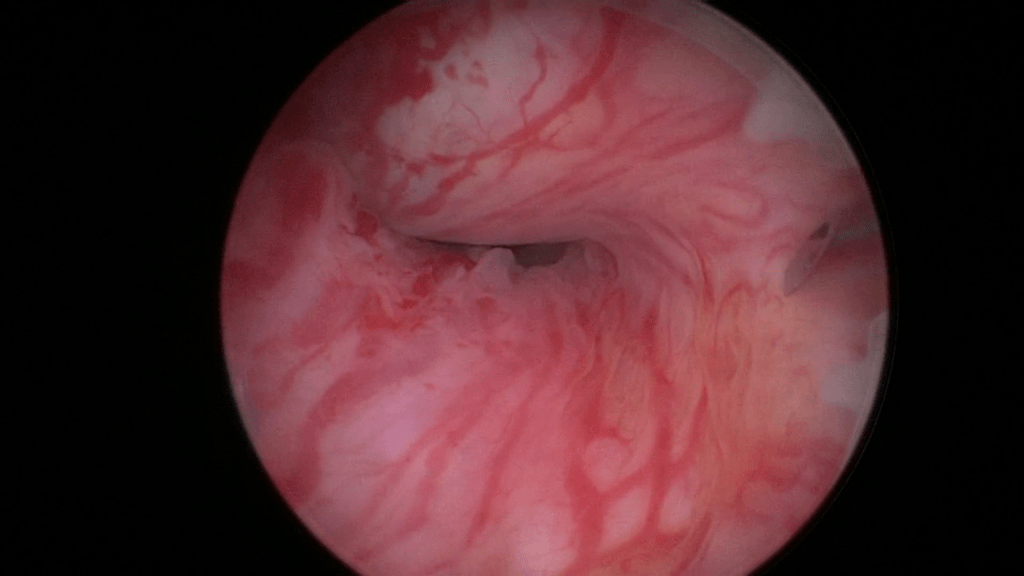

The mid-urethra.

By retracting the cystoscope you can perform an accurate measurement – estimate of the urethra.

The right height to insert the needle is at least 2cm from the bladder neck. This is because after inserting you push the needle up to the first mark (1cm). In other words you are placing the depots 1cm higher than the actual location of the cystoscope.